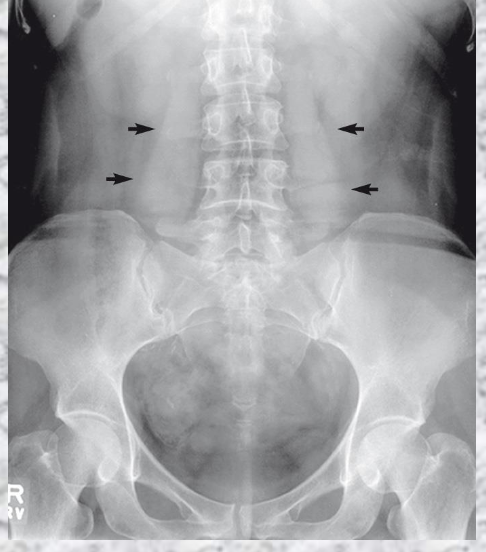

What is seen?

Psoas Muscles